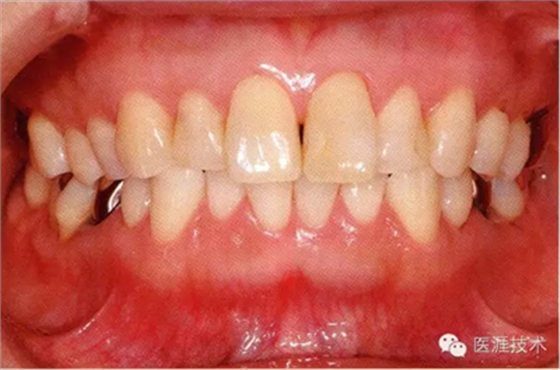

患牙齦炎的牙周組織的臨床圖像

22歲男性牙齦炎的臨床圖像

22歲男性,抽煙(1天約15根,煙齡5年)。刷牙狀態(tài)不佳。抽煙者特有的纖維性牙齦,未見(jiàn)發(fā)紅、腫脹。探針觸診,所有部位均出血。X線牙片未見(jiàn)骨吸收,診斷為牙齦炎。